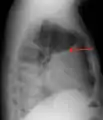

A pleural effusion appears as an area of whiteness on a standard posteroanterior chest X-ray.[12] Normally, the space between the visceral pleura and the parietal pleura cannot be seen. A pleural effusion infiltrates the space between these layers. Because the pleural effusion has a density similar to water, it can be seen on radiographs. Since the effusion has greater density than the rest of the lung, it gravitates towards the lower portions of the pleural cavity. The pleural effusion behaves according to basic fluid dynamics, conforming to the shape of pleural space, which is determined by the lung and chest wall. If the pleural space contains both air and fluid, then an air-fluid level that is horizontal will be present, instead of conforming to the lung space.[13] Chest radiographs in the lateral decubitus position (with the patient lying on the side of the pleural effusion) are more sensitive and can detect as little as 50 mL of fluid. Between 250 and 600mL of fluid must be present before upright chest X-rays can detect a pleural effusion (e.g., blunted costophrenic angles).[14]

Massive left-sided pleural effusion (whiteness) in a patient presenting with lung cancer.

A pleural effusion as seen on lateral upright chest x-ray- Pleural effusion as seen behind the heart.[17]